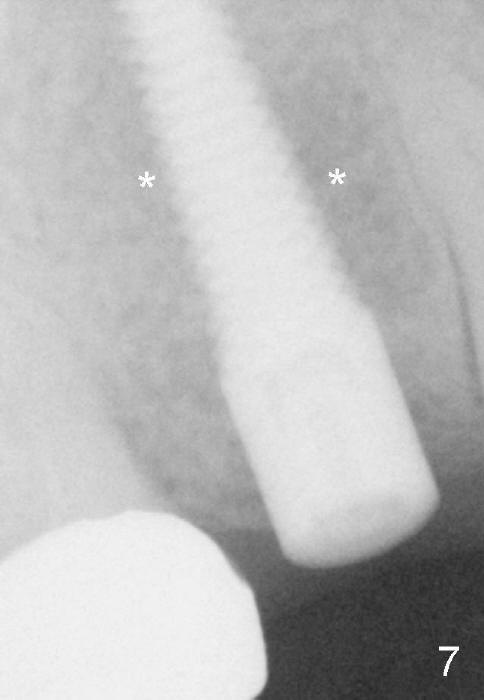

Fig.7 (9 months postop): The bone density around the implant increases (*, compare to Fig.4)